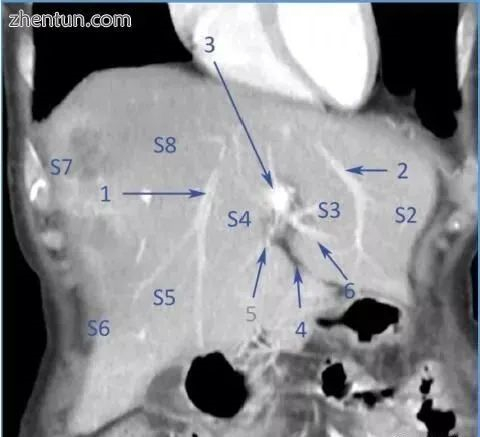

计算机断层扫描,冠状切面,显示肝静脉中间(1)和左(2)。3 - 左门静脉脐部(3),4 - 圆韧带,5 - P4,4段门静脉分支,6 - P3,3段门静脉分支.S2,S3,S4,S5,S6,S7, S8是肝脏部分(图片由布加勒斯特急救医院放射学和意象学系)。